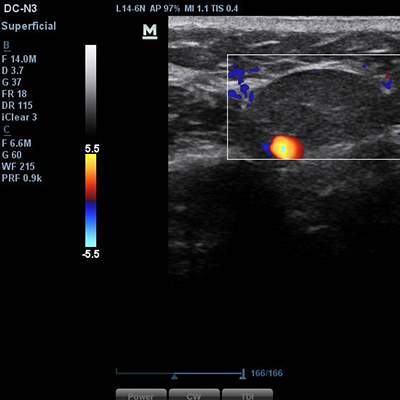

[얼굴이물질제거] 17.01.31 - 이물질제거 - 전후사진

17.01.31 - 이물질제거 - 전후사진